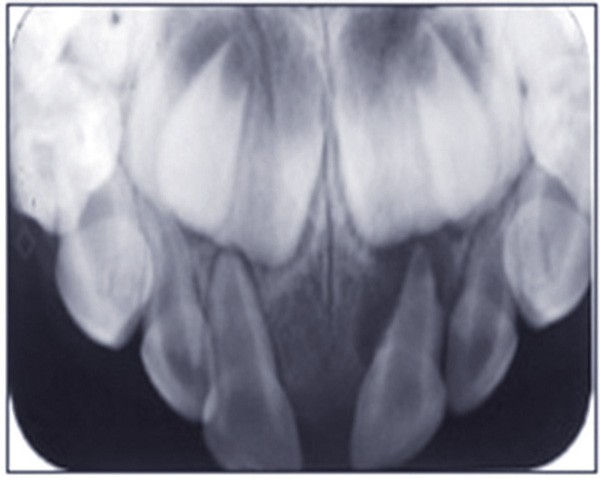

L’omnipraticien est très souvent confronté à cette question lors de sa pratique quotidienne : quel est le bon moment pour adresser les enfants chez l’orthodontiste ? La réponse peut recéler quelques difficultés, car elle est spécifique à chaque enfant. Le temps où il était conseillé d’attendre la denture définitive pour intervenir est révolu : certaines interventions précoces permettent aujourd’hui dans certains cas de raccourcir et de simplifier les traitements orthodontiques. C’est notamment le cas des anomalies transversales, qui sont celles qui sont traitées le plus précocement, dès 6 ans. Ainsi, lors d’anomalie cliniquement évidente, la consultation orthodontique s’impose. Cependant, certaines anomalies sont plus discrètes, et donc plus difficiles à dépister. Une panoramique doit toujours être réalisée en première intention afin de dépister les agénésies. Puis, même en l’absence d’anomalie évidente, il est recommandé d’adresser les enfants chez l’orthodontiste entre 7 et 9 ans : celui-ci sera ainsi à même d’adapter la prise en charge, et surtout l’âge idéal de prise en charge pour chaque patient(fig. 3 et 4).